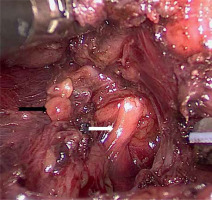

Under single-port endoscopy with carbon dioxide insufflation, the thyroid lobe is retracted medially with a laparoscopic grasper, then the plane between the thyroid and carotid artery is opened. The middle thyroid vein, if present, is divided with the ultrasonic scalpel. The superior pole is pulled inferiorly, and the avascular space between the superior pole and the cricothyroid muscle is opened to expose the branches of the superior thyroid artery and vein, which are transected as closely as possible to the gland to avoid injuring the external branch of the superior laryngeal nerve (Photo 3). Then the superior pole is freed up from its remaining attachments and mobilized inferiorly. The superior parathyroid gland is often identified clearly on the posterior aspect of the superior pole; however, if it is not seen clearly, it is unnecessary to perform further dissection provided that the dissection is kept to the thyroid capsular plane. Attention is redirected to the inferior pole. The inferior thyroid vein is divided close to the thyroid gland. The thyroid lobe is then rolled medially, and the perithyroidal tissue is carefully dissected. The recurrent laryngeal nerve is then identified, usually in the tracheoesophageal groove (Photo 4). The nerve is then traced for a distance of approximately 2 to 3 cm. The inferior parathyroid gland may be encountered and identified during the inferior pole mobilization.

Photo 4

Exposure of the recurrent laryngeal nerve (white arrow) and identification of the inferior parathyroid gland (black arrow)